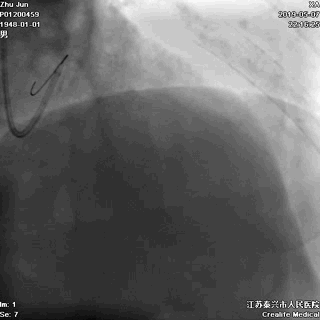

导丝分别进回旋支和前降支

LAD和LCX,任一根血管都不能丢!这一步的价值,就相当于是构筑生命线。